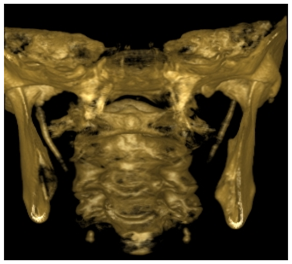

A 23-year-old girl presented to the Department of oral and maxillofacial radiology of the Lebanese University, with a chief symptom of pain in the right neck that worsened on turning the head. The dull, aching pain radiated to the right pre auricular and post auricular areas. The patient also reported intermittent dysphagia, nonspecific for certain food types. On physical examination, tenderness to palpation was elicited bilaterally in the tonsillar fossa region. She had a limited range of neck motion, especially rotation. Neck masses were neither palpable intra orally nor extra orally, and there was no cervical or submandibular lymphadenopathy. The remainder of the neck examination was normal, with a no palpable thyroid and a midline trachea. Radiographic evaluation consisted of a CBCT imaging modality that showed bilateral radiopaque bodies extending from the styloid processes lateral to the mandible (Figure 6,7).

Figure 6 3D reconstruction of the calcifications.